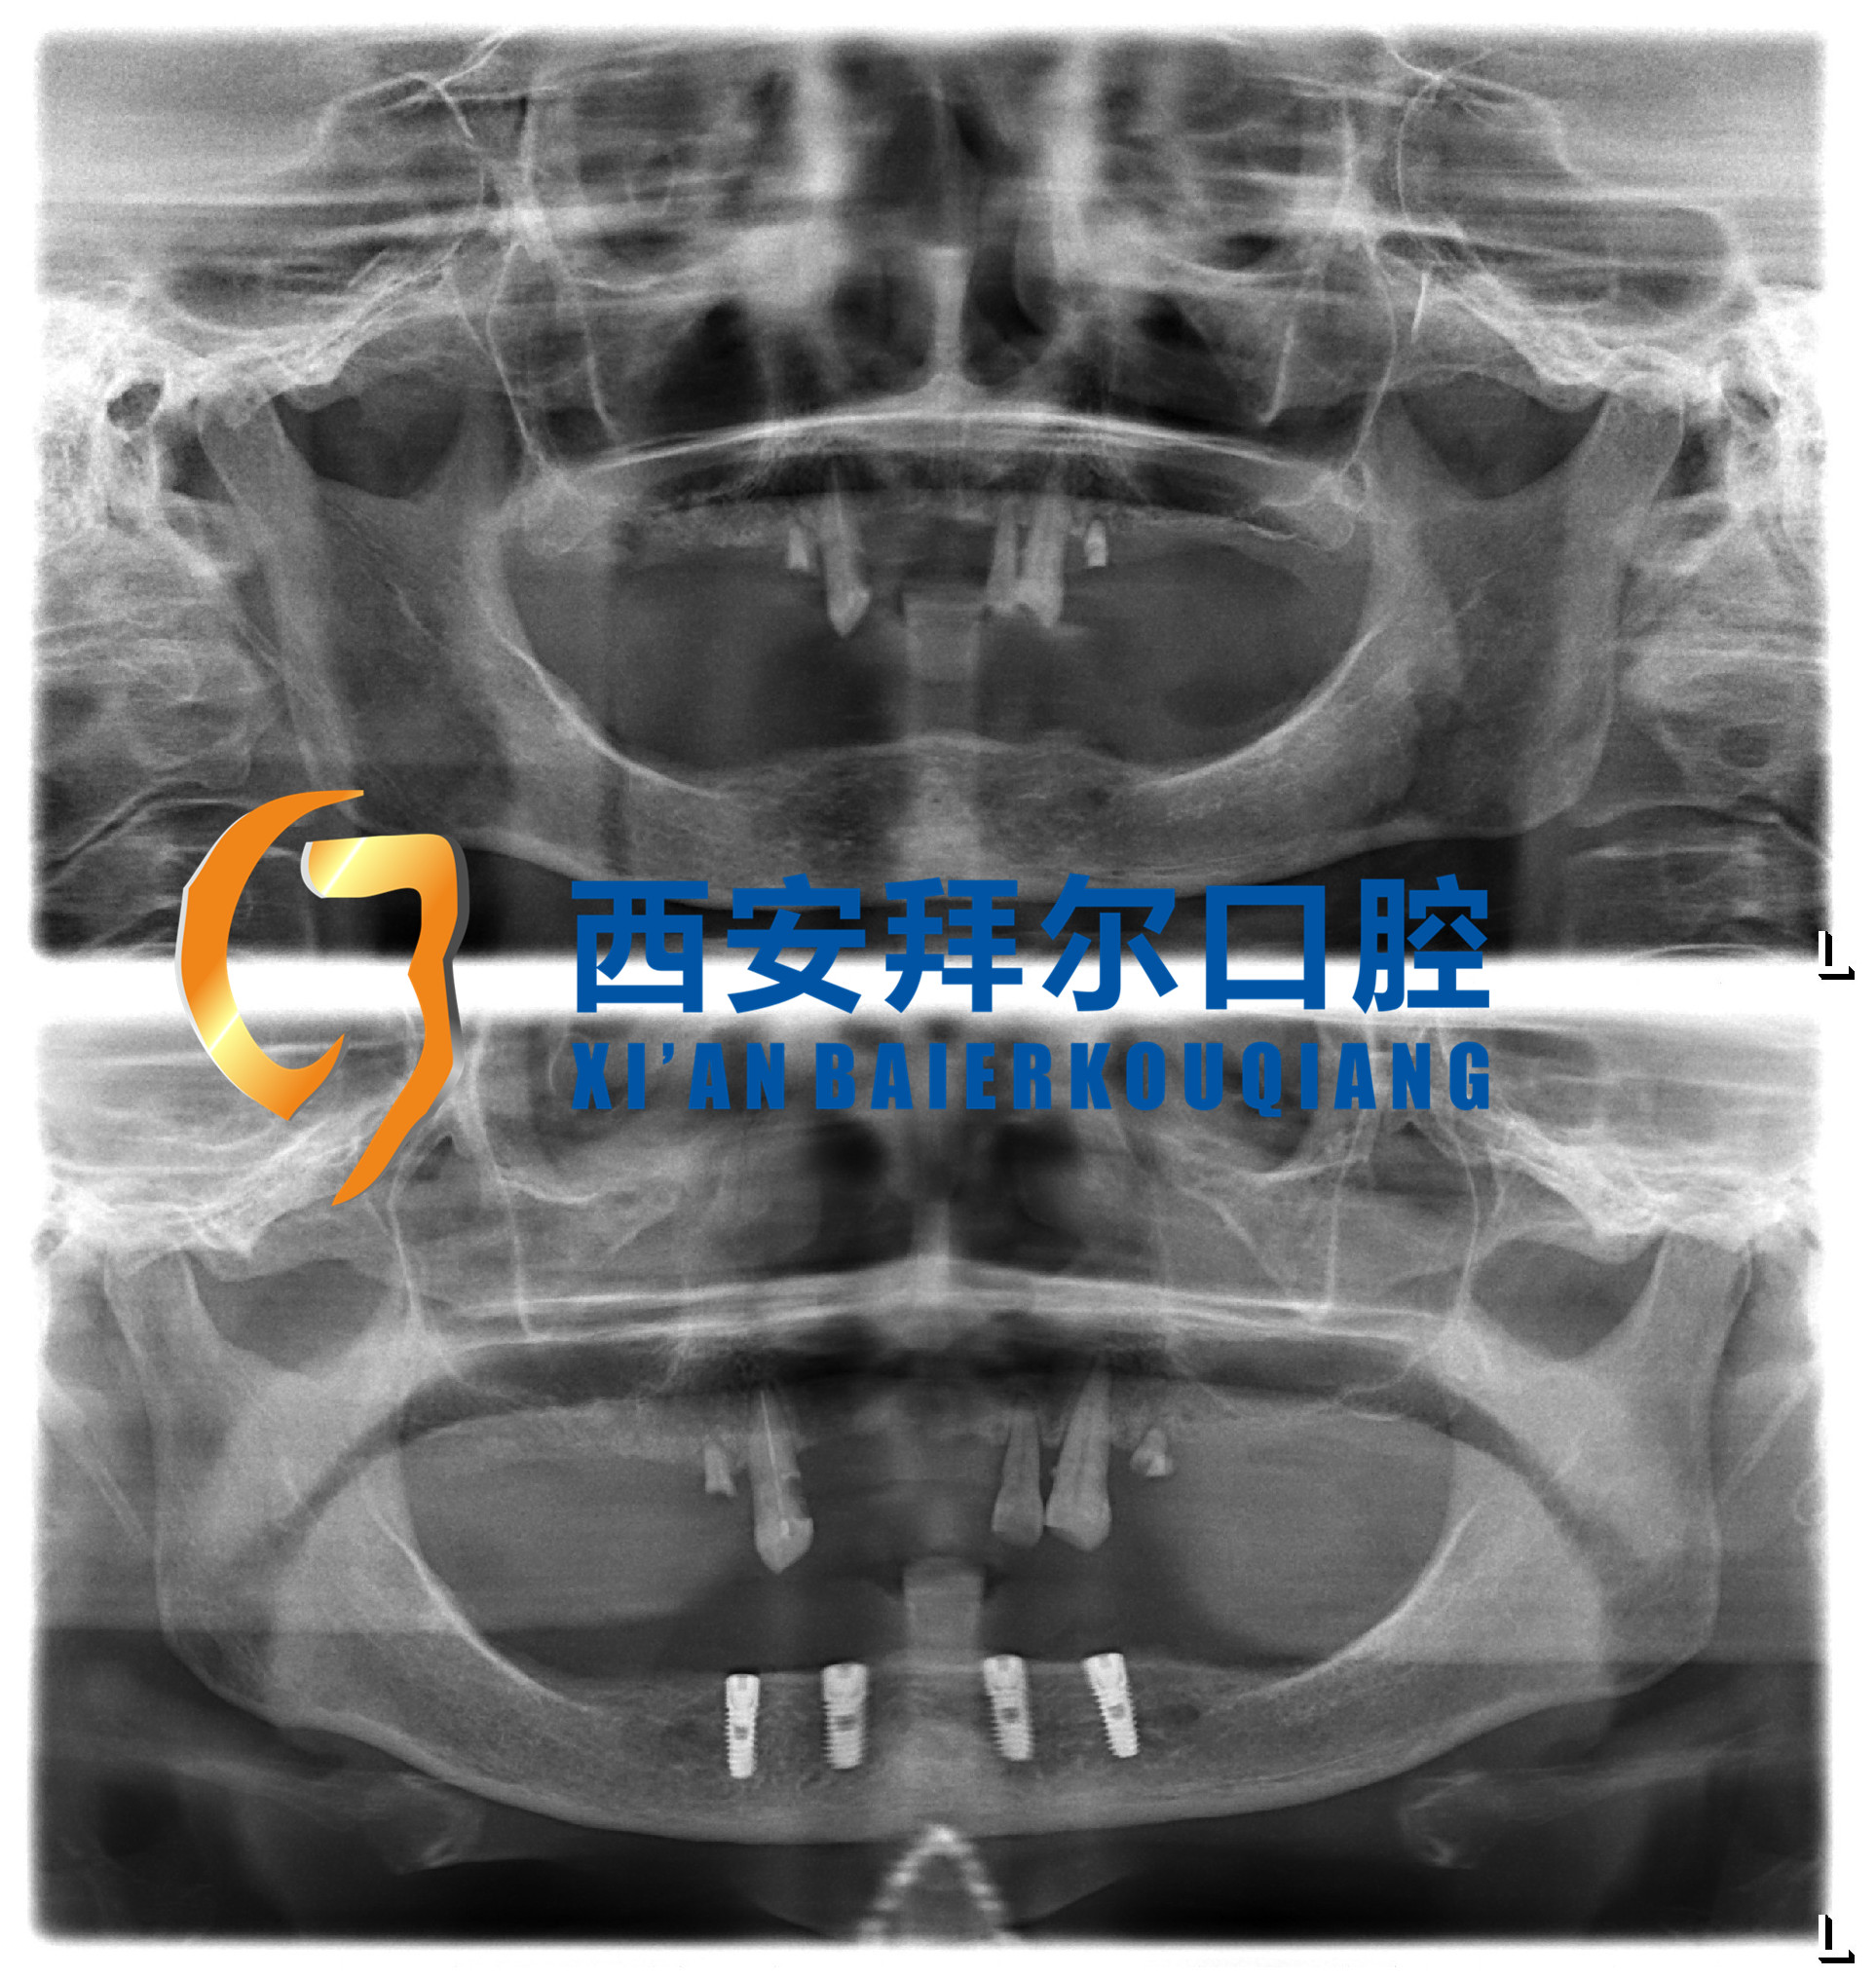

王阿姨女儿看到小区里拜尔口腔医院正在口腔义诊,她就来了兴趣,带着母亲去咨询。跟医生简单交流后,医生检查了王阿姨的口腔,牙齿缺失,符合种植牙的条件,可以考虑种植。女儿就要求医师以最快的速度给母亲预约、做手术。半年过去了,王阿姨重获新牙。上个月,王阿姨带着朋友过来补牙,她说去泰国刚回来,兴奋地和我们讲着当地的故事。她说牙齿好了咀嚼好,胃口也好了,当地美食统统吃一遍。看她的气色特别好,整个人好像年轻了十岁。